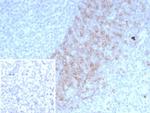

IgD (Immunoglobulin Delta Heavy Chain) (B-Cell Marker) Antibody in Immunohistochemistry (Paraffin) (IHC (P))

IgD (Immunoglobulin Delta Heavy Chain) (B-Cell Marker) Antibody (3495-MSM4-P1) in IHC (P)

Formalin-fixed, paraffin-embedded human lymph node stained with IgD Mouse Monoclonal Antibody (IGHD/4967). HIER: Tris/EDTA, pH9.0, 45 min. 2°C: HRP-polymer, 30 min. DAB, 5 min. {{ $ctrl.currentElement.advancedVerification.fullName }} 验证信息 View more